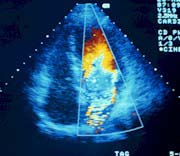

• transtorakalnu ehokardiografiju